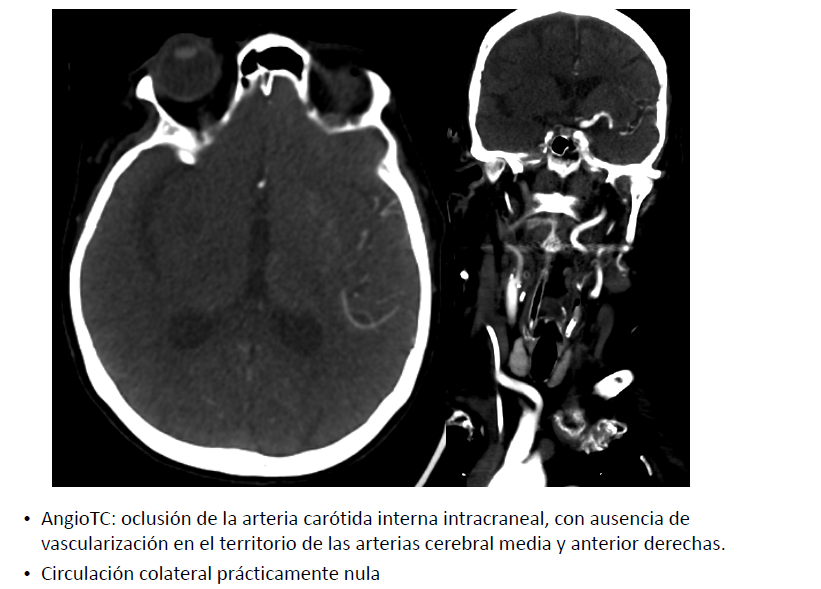

Complicación hemorrágica masiva tras trombectomía mecánica con aspiración en paciente añosa con antecedente neoplásico